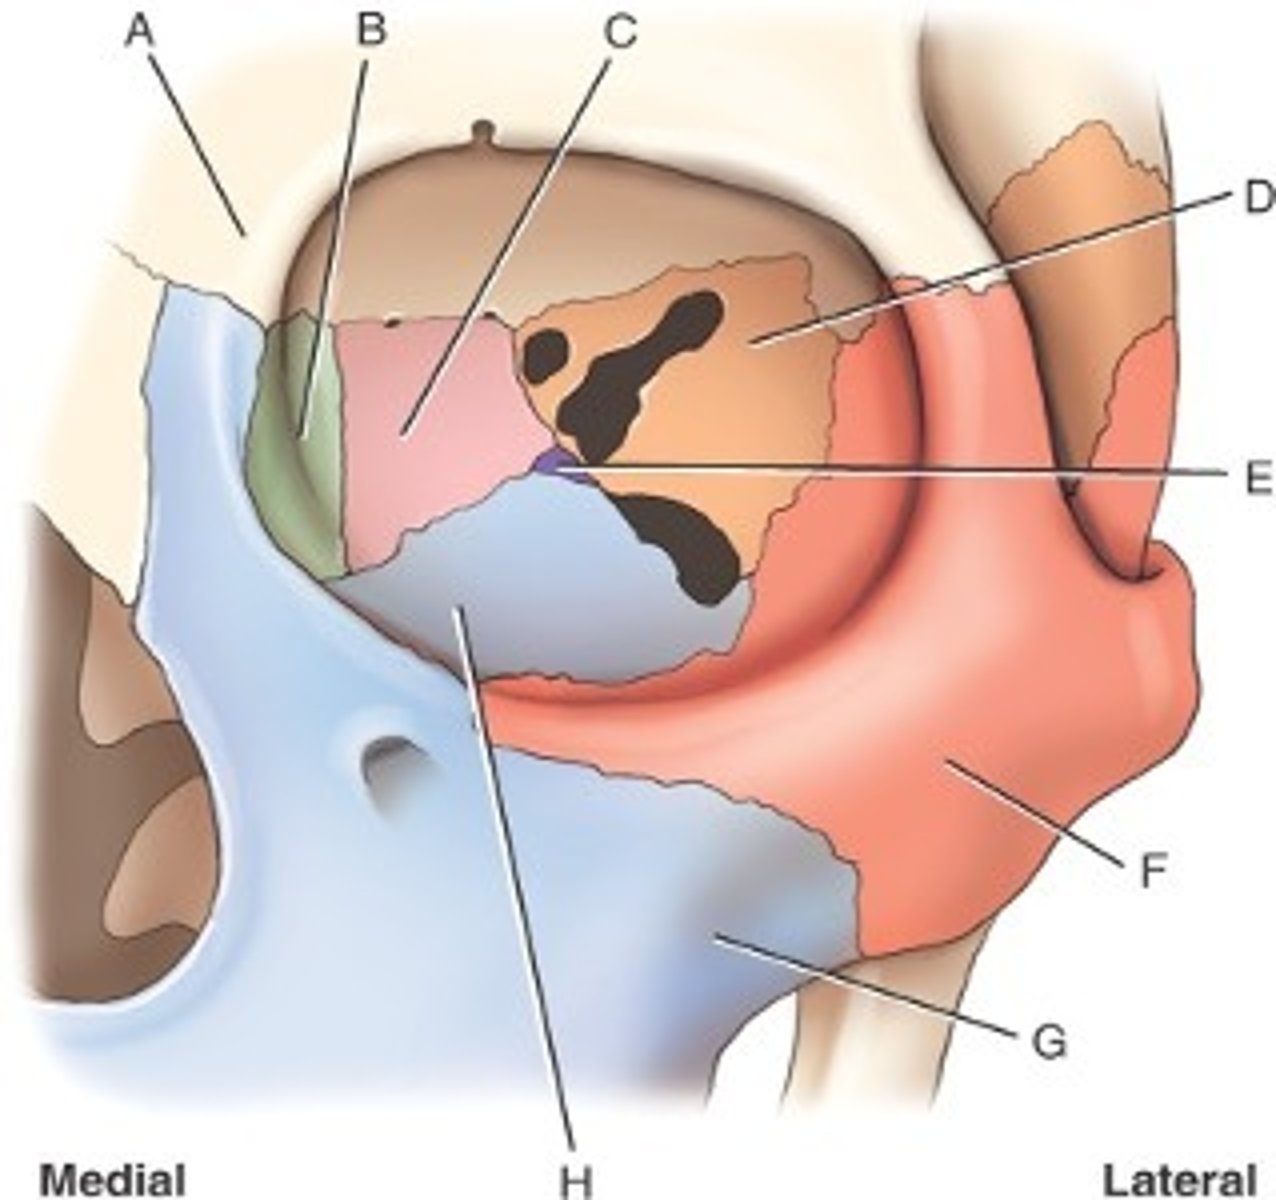

What is B

frontal bone

What is A

ethmoid

What is C

sphenoid

what is D

Palatine

What is E

Zygoma

What is F

Maxilla

What is G and H

optic foramen in orbit

sphenoid strut